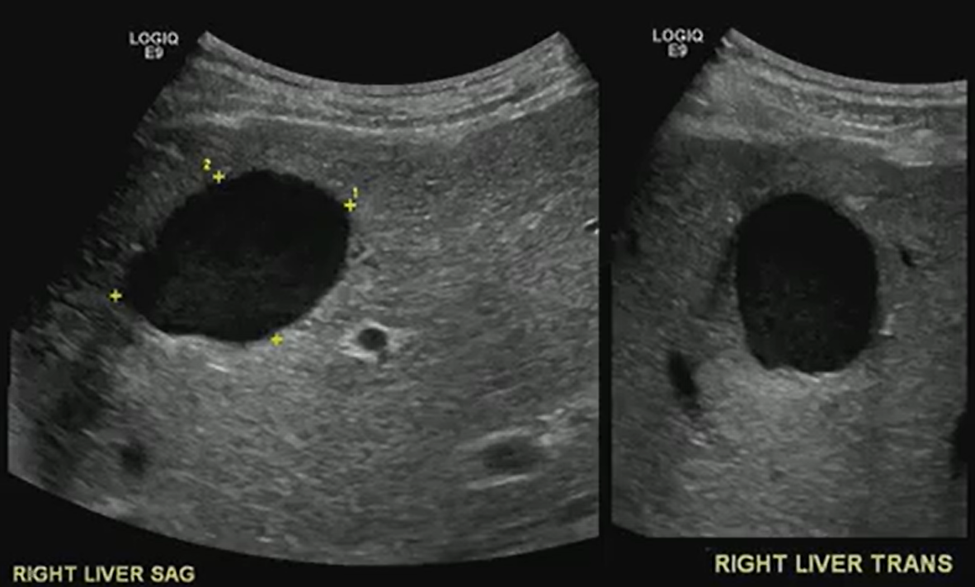

A benign-looking liver lesion turned out to be a hepatic artery pseudoaneurysm—all thanks to color Doppler.

What looks like a simple hypoechoic cyst on ultrasound may hide a critical vascular pathology. Color Doppler is essential for distinguishing cystic lesions from vascular anomalies like pseudoaneurysms.